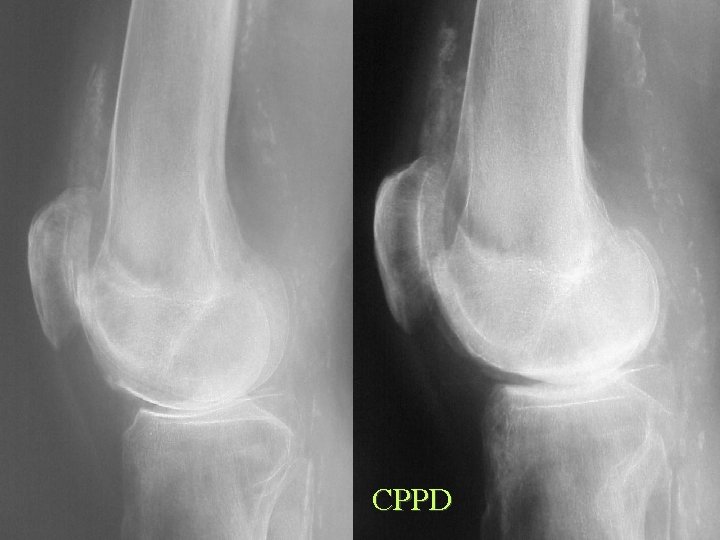

CPPD

Calcification By site Articular cartilage • Osteoarthrosis • • CPPD HADD Hyperparathyroidism Haemochromatosis